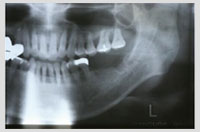

症例3 抜歯と同時埋入した症例 年齢63歳 男性

初診時の状況

・右上4番の痛み

・歯根歯折があり抜歯と決定

・前後の歯を削りブリッジタイプのかぶせ物を検討したが、健康な歯を切削するのは希望しないとの事でインプラントを選択